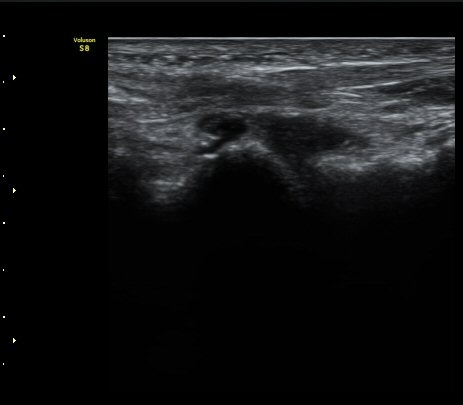

Á¾°ñÀÔ¹æ°ñÀÎ´ë ¿ÜÃø Á¾´Ü¸é°Ë»ç¿¡¼­ ¼ö¾×Àú·ù°¡ °üÂûµÊ(»çÁø 6, 7).